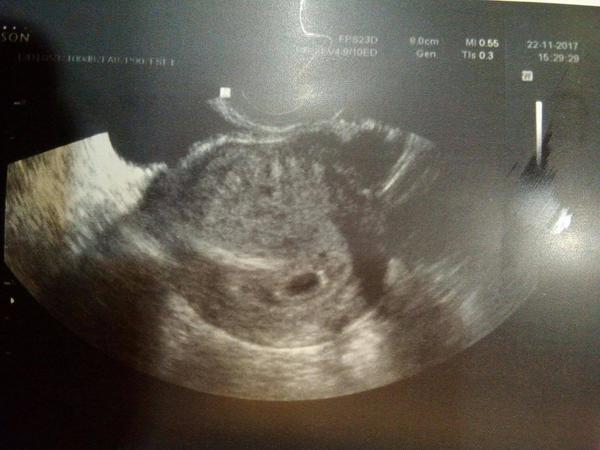

Překrásná zpráva, čekáme miminko. Testíky krásně potvrzené a hurá k dr na 1.UZ. Byl v 5+4tt kdy byla vidět jedna dutinka (prázdná) a doma jsem si na fotce všimla ještě jedné miniaturní dutinečky o které dr nic neříkal.

Další kontrola v 7+2tt. Na uz krásná dutinka s fazolkou a srdíčkem. Nad tím byla další dutinka, ale o doooost menší, ale též měla embryo. Jenže dr se o ni ani nezmínil a až když jsem se zeptala tak hned odpověděl, že dvojčátko, které se nevyvíjí, tudíž syndrom mizejícího dvojčete. Takže šok v šoku. Nic víc neřešil. Mám průkazku, tam jen zmínka o jednom.

Ale nechápu, jak když to druhé též vyrostlo a to snad i o víc, jak první, tak jak může být nevyvíjející?? Hlavně jsem i četla, že jsou případy, kdy je druhé mimi mladší o několik dní či i týdnů.

Přidávám i fotečky a moooooc prosím o vysvětlení, uklidnění či cokoliv, co mi to pomůže pochopit.

@pitryludvikova no právě že stejná nebyla. Od toho prvního UZ se ohromně zvětšila, jen prozatím neměla srdíčko. Jen mne zaráží, že má malý váček, ale jinak je stejně velké ... fakt to mám strašně pomotané. Kdyby nerostlo neřeknu, ale vyrostlo opravdu hodně... ta kvalita je špatná, pak dopošlu lepší

@tynka07 tak to tezko rict, je mozne ze je jen mladsi treba o 14 dnu...